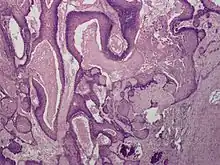

Proliferating trichilemmal cysts (also known as a "Pilar tumor", "Proliferating follicular cystic neoplasm", "Proliferating pilar tumor", and "Proliferating trichilemmal tumor"[2]) are a cutaneous condition characterized by proliferations of squamous cells forming scroll-like structures.[2][3]: 678